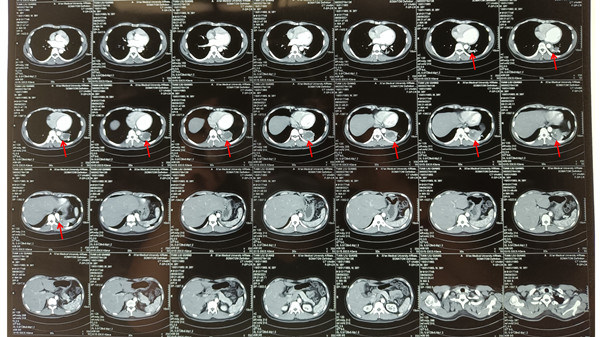

患者田某某,男,38岁,因“发现肺肿物5日余”于2021年09月10日入我院胸外科。入院后行胸部增强CT提示:左肺下叶背段、后基地段实行囊块,多考虑肺隔离症伴感染,合并动脉导管未闭。心脏彩超示:大动脉短轴切面显示肺动脉根部与降主动脉之间可见一管状结构,CDFI:大血管水平可见左向右红色分流彩束,宽约5.7mm,诊断为动脉导管未闭。经胸外科全科讨,并邀请麻醉科吕建瑞教授会诊,最终决定在全麻下行胸腔镜下左肺下叶切除+动脉导管未闭结扎术。

图2

经过充分的术前准备,9月14日上午,在麻醉科进行全身麻醉后,随后胸外科李少民主任团队完整切除了(见图2),并成功结扎动脉导管(见图3),手术过程顺利,历时2小时,术后患者生命体征平稳,顺利拔除气管插管后安全返回胸外科病区,目前患者病情稳定。